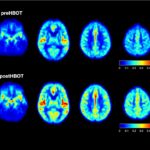

Brain Scans – no annotations (1)